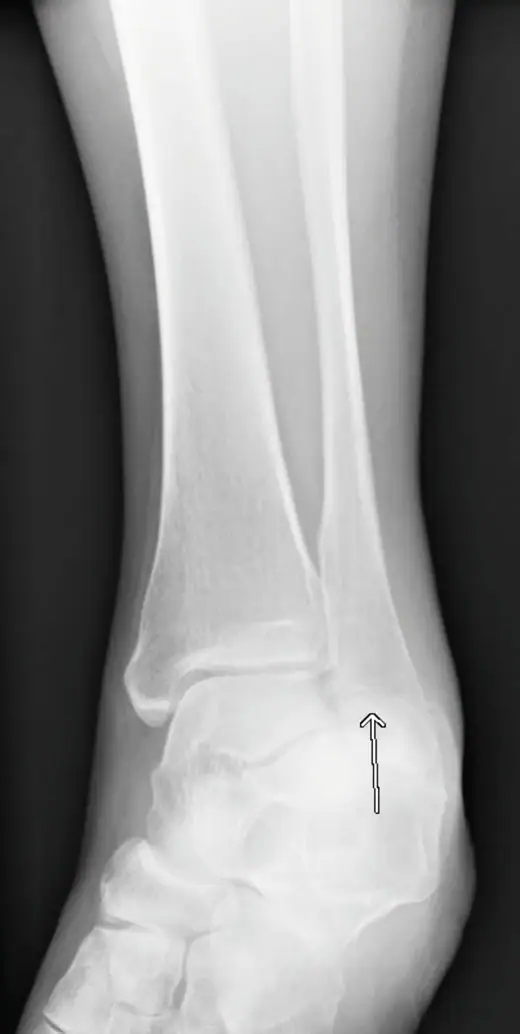

Diagnosis: The x-ray reveals a horizontal relatively nondisplaced fracture (arrow) of the lateral malleolus below the level of the talar plafond representing a Weber type A fracture or Lauge-Hansen supination adduction Stage I injury. A splint and referral to orthopedics for further management is appropriate for this patient.